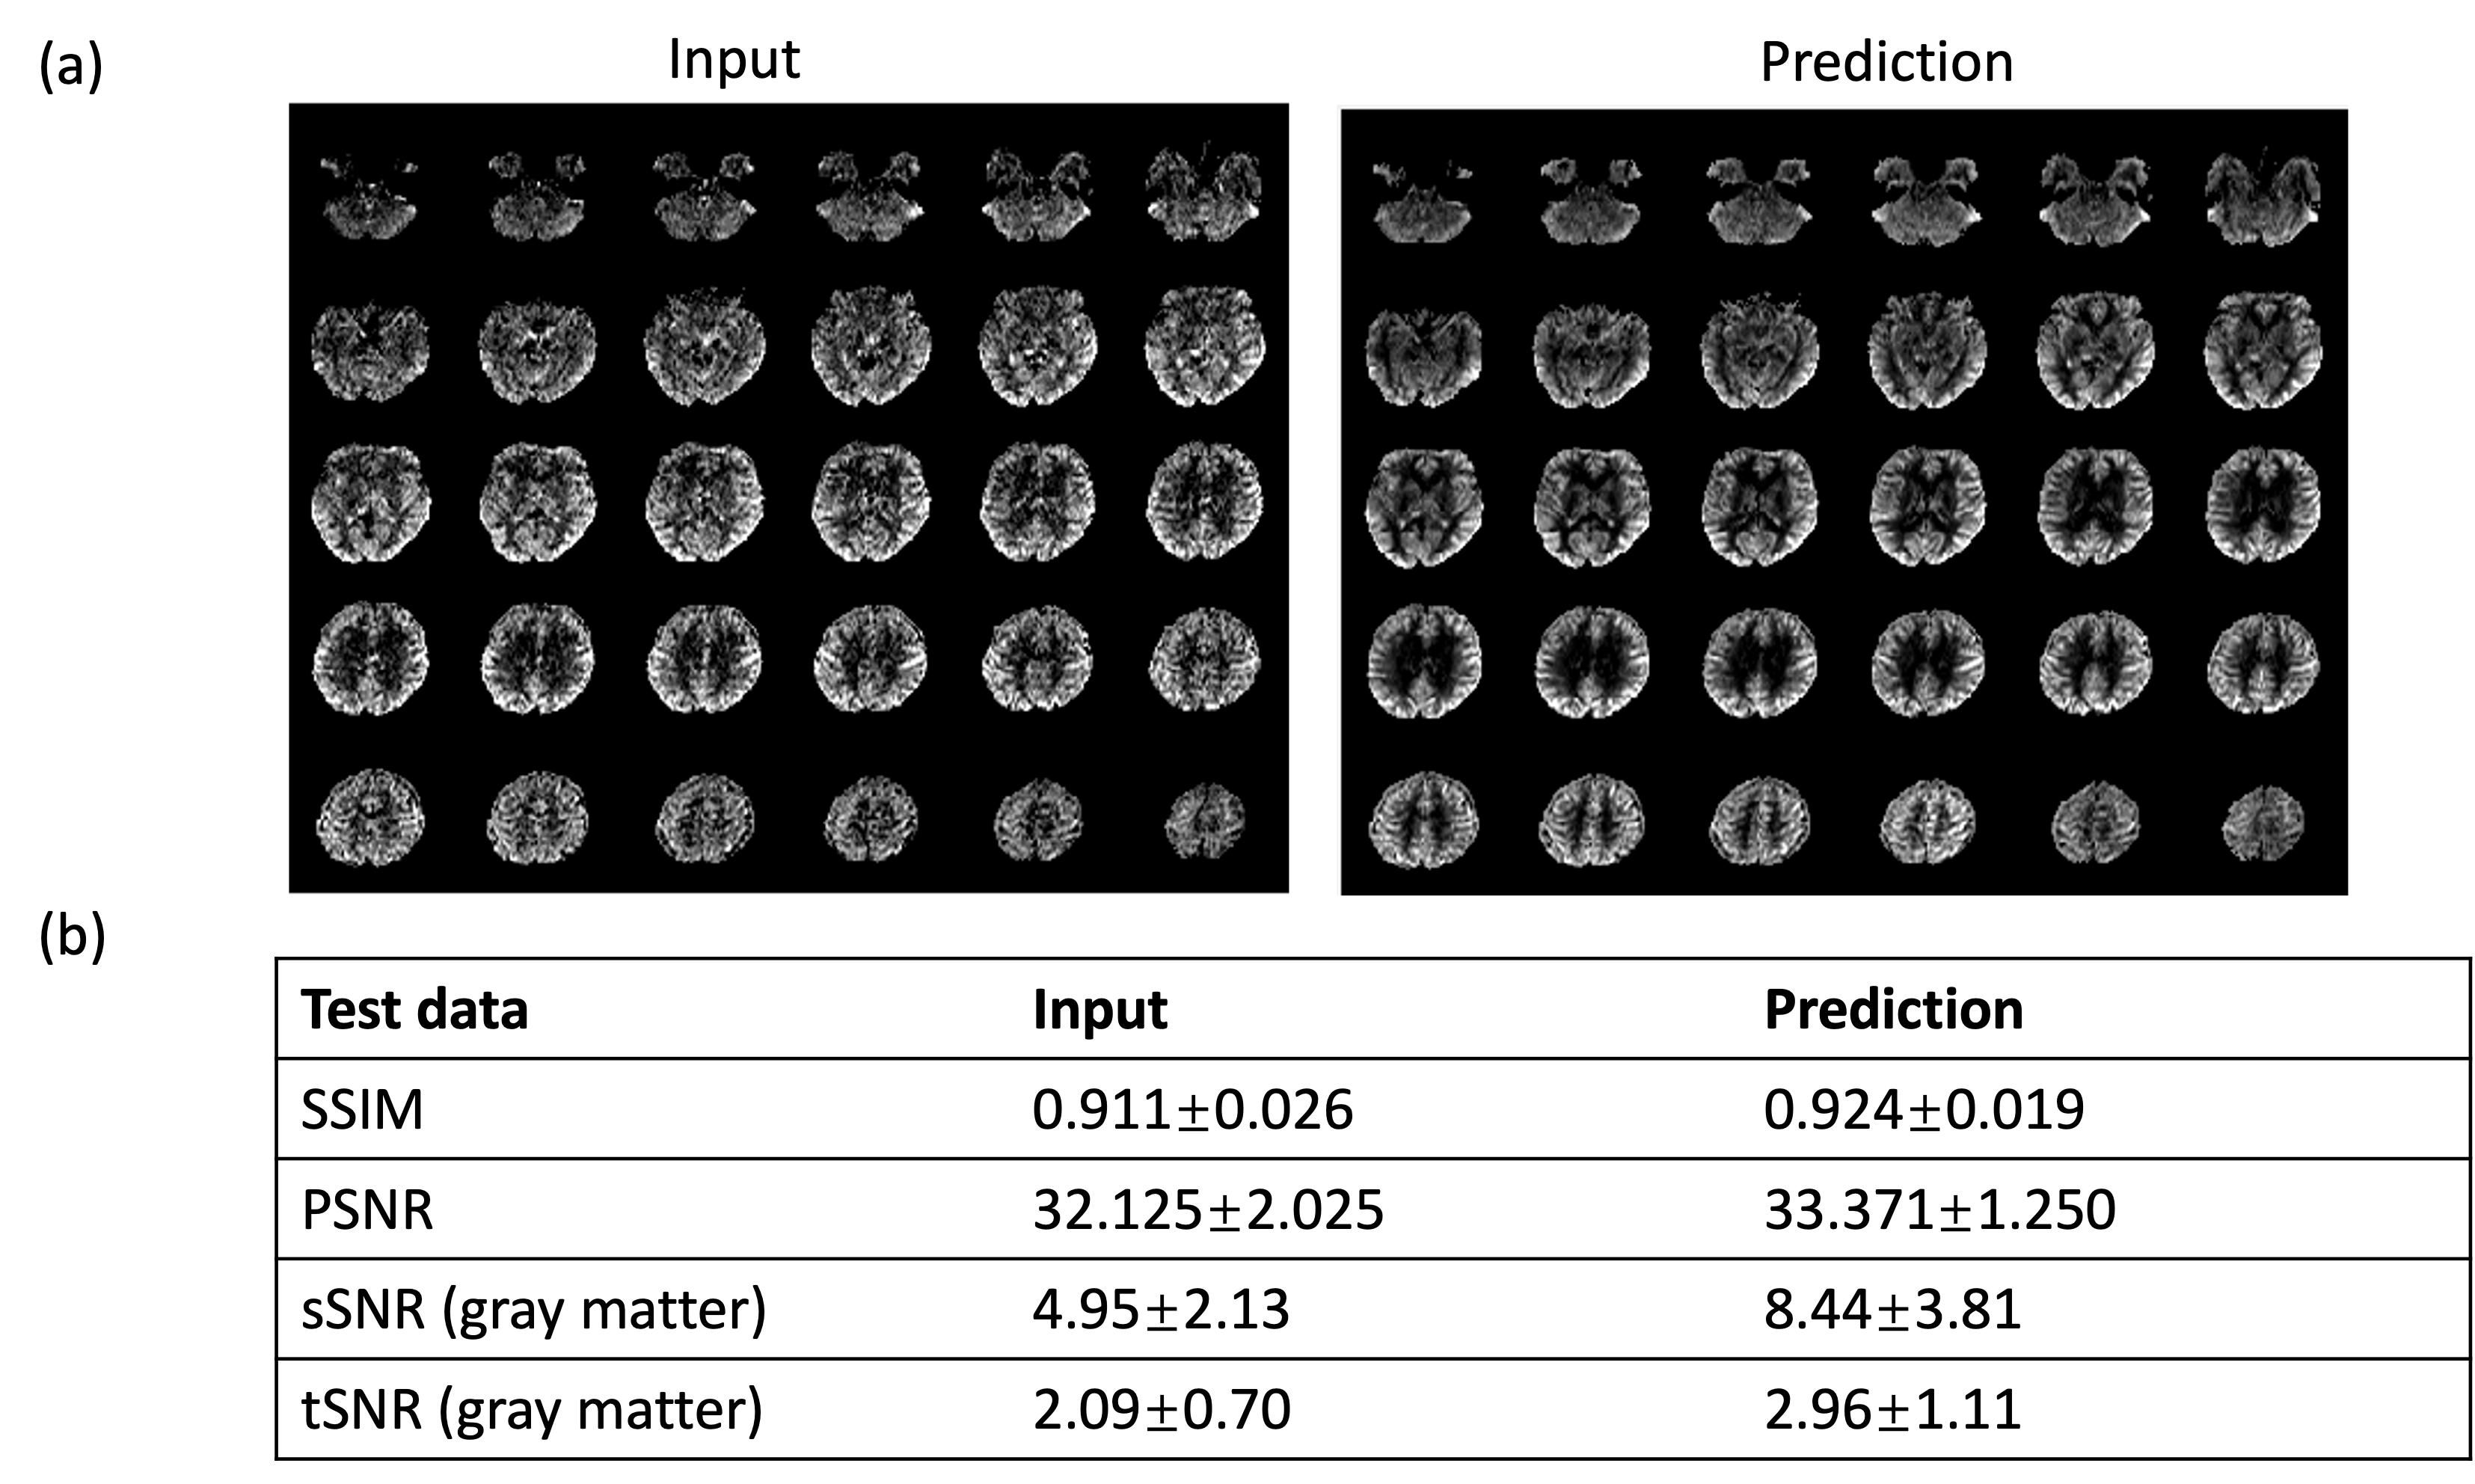

Figure 2 shows the results for the first test dataset, the image for the DL prediction has improved SNR compared to the input. The similarities metrics are also consistent with the visual quality, SSIM and PSNR after DL denoising were improved by 2% and 7.6%, while spatial and temporal SNR were improved by 181% and 134% respectively. Figure 3 shows the results for the second dataset, SSIM and PSNR were improved by 1.4% and 3.9%, while spatial and temporal SNR were improved by 71% and 42% respectively. Figure 4 shows the results for the multi-delay dataset. DL prediction has improved the SNR for perfusion images at each PLD, and improved SNR for the fitted CBF and ATT maps. Figure 5a shows that the global CBF values calculated from the DL prediction is highly consistent with those from the single-delay input images. Figure 5b and 5c show that the fitted CBF and ATT values from the DL predicted multi-delay perfusion images are also consistent with those fitted from the input images.

Figure 2. The input and prediction on the test dataset (same cohort as the training data). (a) Input perfusion image and the DL denoised perfusion image of one subject. The DL denoised image has higher SNR compared to the image. (b) The quantitative results of the input and DL-predicted image. DL denoised image has higher SSIM and PSNR compared to the input image, as well as higher spatial and temporal SNR.